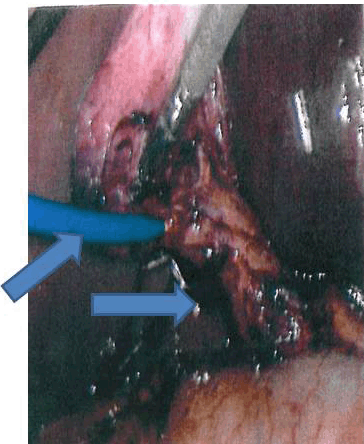

Figure 2: Intraoperative monograph demonstrating dilated common bile duct and catheter inserted in cystic duct for cholangiography, duct exploration and stone extraction.

The patient was taken to the operating room where she underwent laparoscopic cholecystectomy with intraoperative cholagiogram and laparoscopic common bile duct exploration and stone extraction. Post operatively, the patient recovered uneventfully with her liver enzymes trending downwards and relief of her right upper quadrant abdominal pain. Patient was discharged on post operative day two in good condition.

Although the first line of management of bile duct stones usually includes endoscopic retrograde cholangiopancreatography (ERCP) with or without sphincteromy and biliary stent placement, complications such as, pancreatitis, bleeding, and visceral or ductal perforation are serious potential concerns. Prior to cholecystectomy, ERCP is indicated in the presence of cholangitis, persistent jaundice, and choledocholithiasis on ultrasound, or the combination of dilated ducts and abnormal liver function tests (LFT's). [5] [6] When endoscopic stone removal fails, especially during pregnancy, biliary decompression still has to be and usually can be achieved via endoscopic biliary stent placement by skilled gastroenterogist. Satisfactory drainage was achieved through the biliary stent. When available, balloon lithotripsy and debulking of the common bile duct stone is another option in the treatment armamentarium. However, this modality of treatment may not be readily available at all medical facilities or institution, which limits its widespread and/or universal application. Although it has been shown to be an effective treatment option, lithotripsy was unavailable at the institution where this patient received her care. [7] [8] [9] Thus, other minimally invasive surgical treatment options for CBD stone extraction such as laparoscopic stone removal using a fogarty cathether or dormia basket technique should be considered. In this particular case, we were successfully able to remove the impacted stone and clear the CBD utilizing a combination of balloon extraction and a forward flushing technique via the cholangiocatheter via the cystic duct stump. After the stone was removed the post-procedure cholangiogram revealed adequate clearing of the biliary tract in our patient. Thus, there was no need for the intra-operative placement of a T-Tube, as the endoscopically placed internal biliary stent remained in the CBD. These procedures are followed by laparoscopic cholecystectomy during the same operative setting, which is usually performed in the immediate post-partum period after successful delivery. [10] Even though open cholecystectomy with common bile duct exploration is a viable option, additional consideration should be given to the possibility of compromising the mother's ability to care for her newborn infant during the postoperative convalescence period. Therefore, we recommend gallbladder removal and stone extraction utilizing minimally invasive techniques whenever possible to minimize postoperative morbidity after delivery and to expedite recovery. [11]